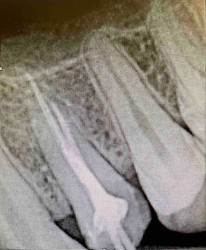

• пломбировка каналов с последующим рентген конторолем;